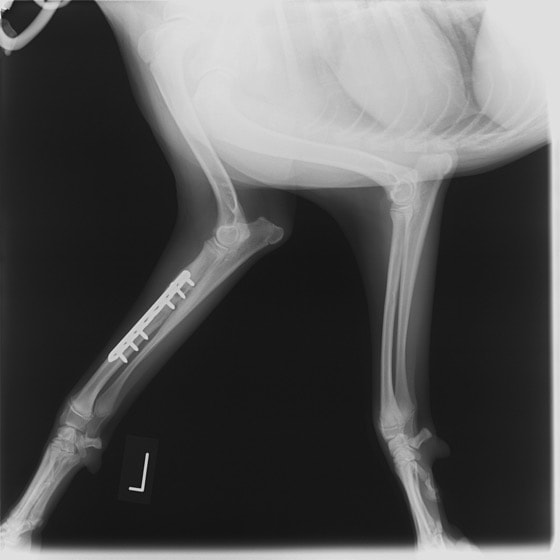

トイプードル 右遠位橈尺骨短斜骨折のALPSによる内固定